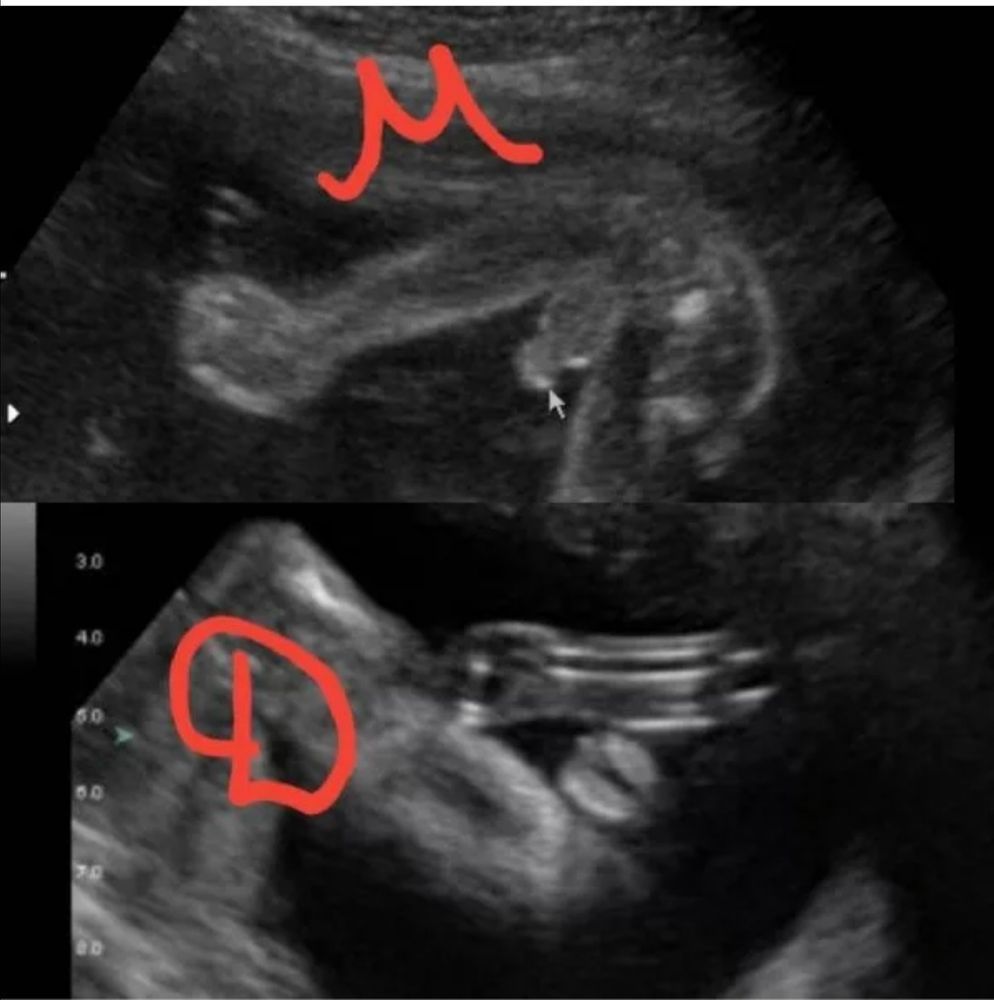

Александра Мищук, посмотрела в интернете сейчас, вроде у мальчиков не так совсем, и яички ещë не опустились на таком сроке. Склоняюсь, что всë таки девчачий "пирожок". Тем более врач девочку увидела, она то точно со всех ракурсов видела. Изображение Изображение

06.12.2024